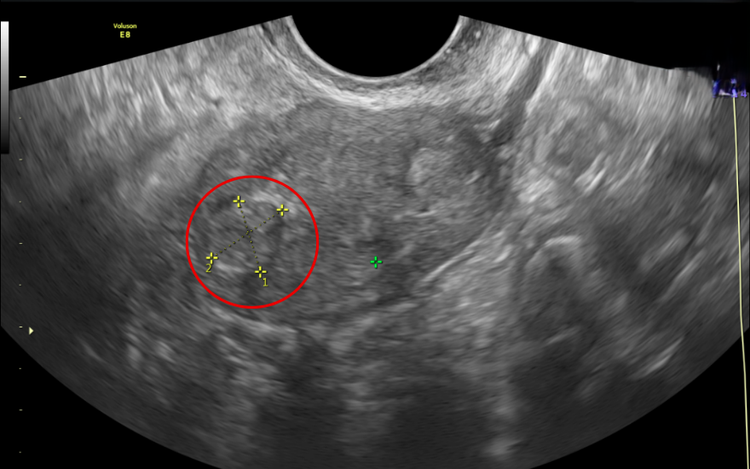

Kết quả thăm khám cho thấy chị H. mắc sa sinh dục độ II–III. ThS.BSCKI Bùi Xuân Quyền, Trưởng khoa Sản Phụ khoa, BVĐK Hồng Ngọc Phúc Trường Minh cho biết: “Khi đến khám, người bệnh trong tình trạng sa sinh dục tương đối nặng, gần như toàn bộ vùng chậu bị tụt xuống. Khi kiểm tra, chúng tôi còn phát hiện thêm polyp cổ tử cung. Với mức độ tổn thương này, người bệnh không còn khả năng điều trị bảo tồn mà bắt buộc phải phẫu thuật cắt bỏ tử cung hoàn toàn”.

Chị H. được chẩn đoán sa sinh dục độ II - III (mức độ trung bình - nặng) và Polyp cổ tử cung - Ảnh BVCC